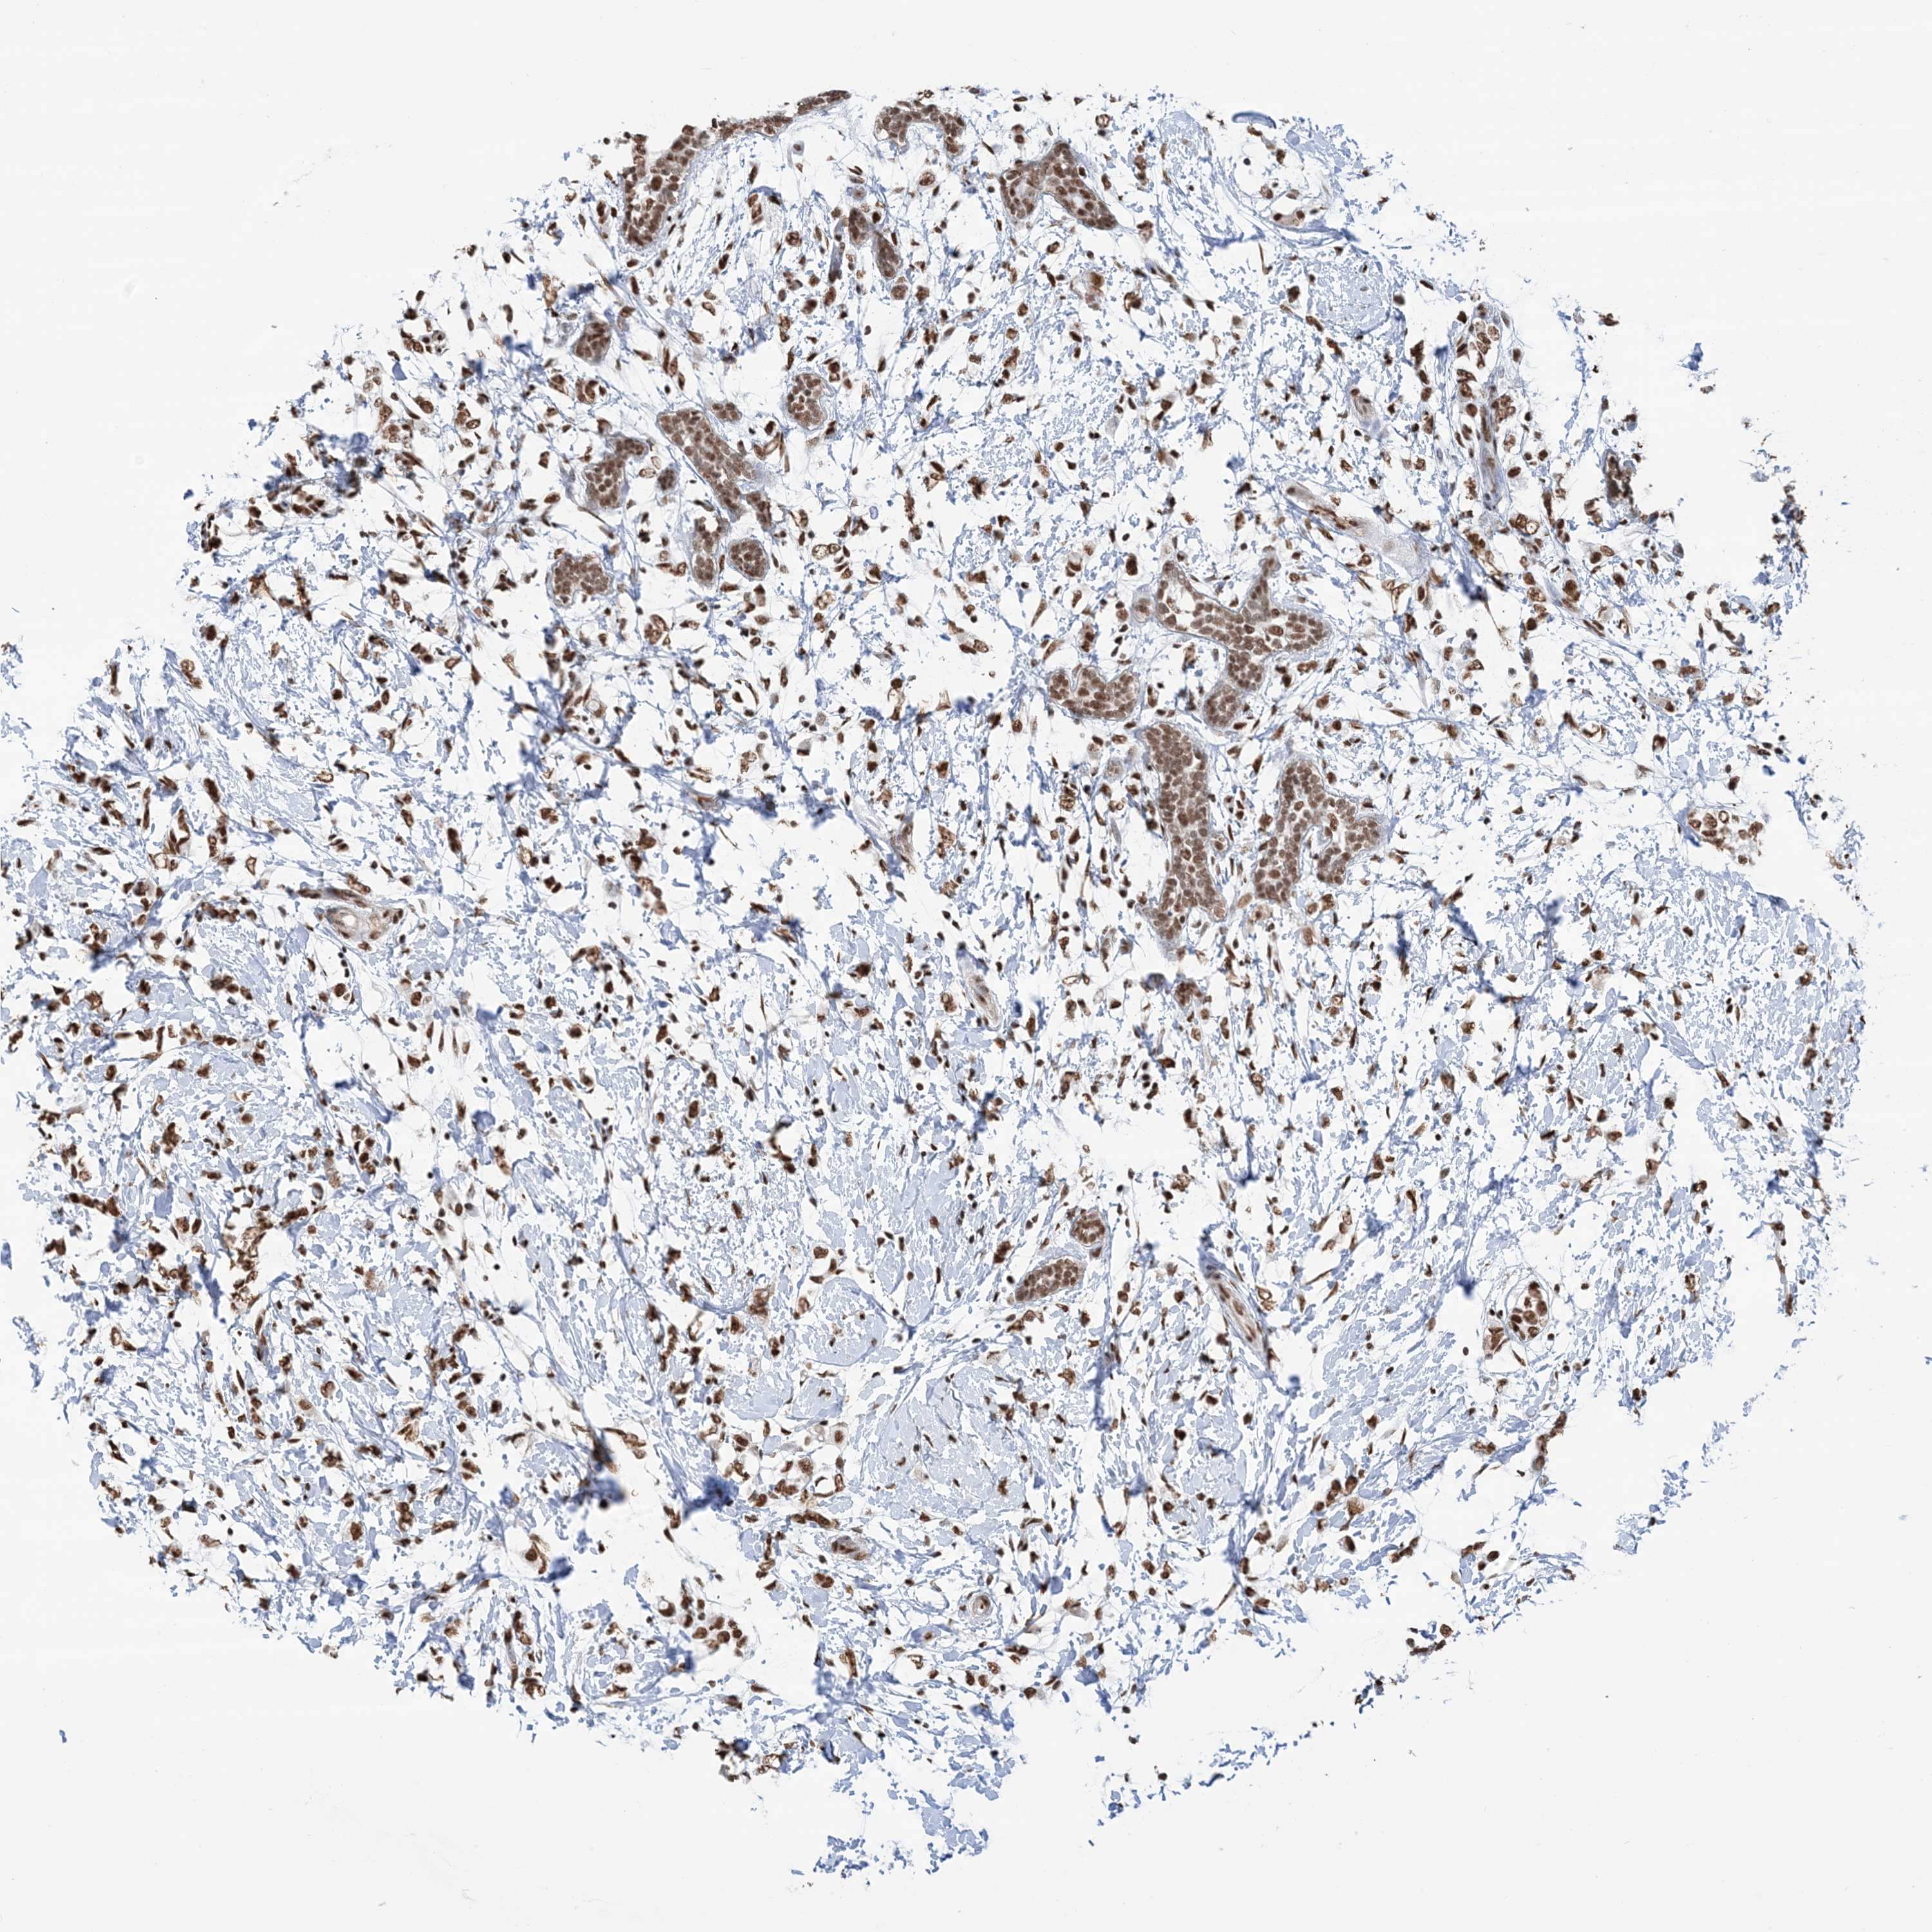

CANCER BREAST CANCER Show tissue menu

BRCA TCGA BRCA VALIDATION PROTEIN EXPRESSION

Breast cancer

Human cancer

Breast invasive carcinoma